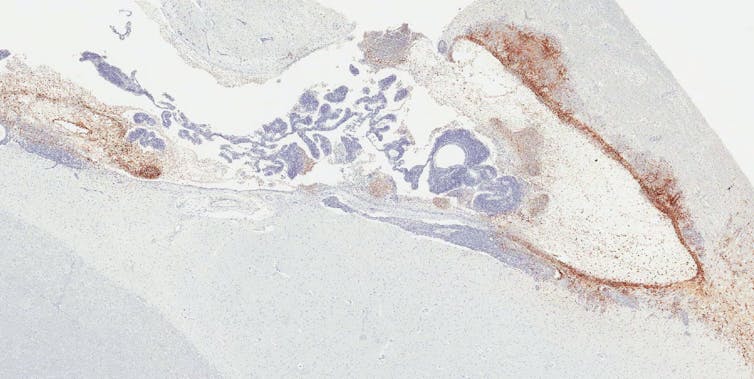

When we looked more closely at the tissues of different organs under a microscope, however, we found that about 20% of recovered monkeys still had visible Ebola virus located exclusively in the ventricular system of the brain. This brain region produces, circulates and stores cerebrospinal fluid, which protects, supplies nutrients to and removes waste products from the brain.